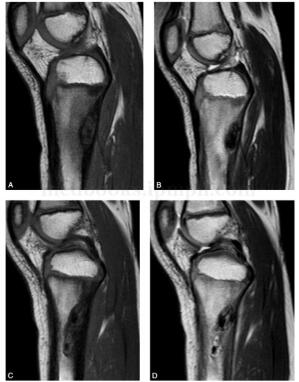

图5 MR:左胫骨近段见多发长椭圆形短T1短T2信号影,部分信号增高,周围见低信号影环绕

(三)MRI

MRI检查多数病灶在T1WI及T2WI上均呈低信号,反映了内部成熟的纤维组织,如细胞成分明显多于胶原纤维,则可在T2WI上表现为高信号。增强扫描可出现均匀、不均匀、边缘及分隔强化。